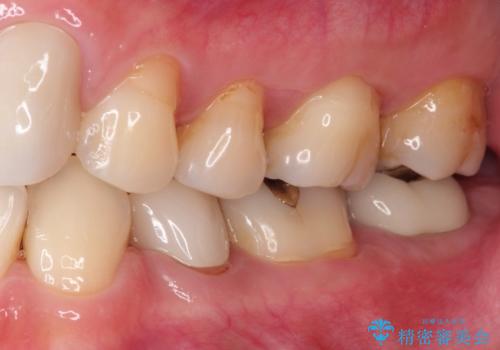

奥歯が痛い。根管治療からセラミッククラウン

咬合力が強くかかる部分には欠けるリスクのほとんどない金属を用いることが最良ですが審美性に劣ります。

今回は白い材料での修復を希望されたため、セラミッククラウンにて治療を行いました。